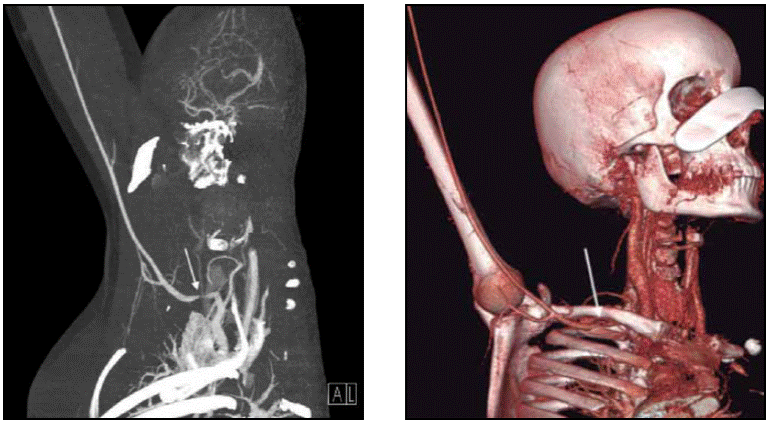

Angio TAC de EESS: Estrechamiento localizado de la arteria subclavia derecha, a unos 3 cm de su origen en un segmento aproximado de 12 mm coincidente con su paso entre la clavícula y el primer arco costal, con una disminución de la luz arterial valorable en área del 85% en diámetro. Hallazgos compatibles con: síndrome del estrecho torácico superior de origen vascular y estenosis de la arteria subclavia derecha.